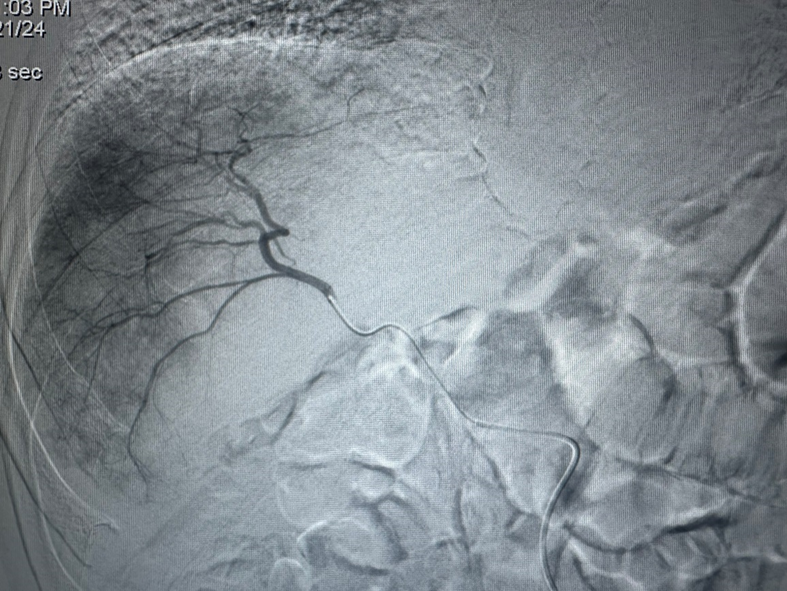

图1:HAIC术中将导管超选择至肿瘤供养血管

患者男性,84岁,为一名僧侣,因“间断右上腹痛1年,加重7天”入院。患者于1年前无诱因出现间断性右上腹痛,未予诊治。7天再次出现右上腹及剑突下痛,疼痛放射至肩背部及后腰部,伴有腹泻,就诊于当地县医院,查超声为:胆囊多发结石,胆囊壁增厚。为进一步治疗就诊于拉萨市人民医院普外科,查腹部增强CT提示:胆囊癌伴临近肝脏侵犯、肝内多发转移,肝门区、门腔间隙及腹膜后大血管周围多发淋巴结转移。因为肿瘤晚期,已失去手术切除机会。遂请来自北京佑安医院的援藏专家李建军主任医师会诊,结合患者年龄、病史及影像结果,考虑患者为胆囊癌,伴肝内多发转移及淋巴结转移,且肿瘤为乏血供,李建军主任医师建议行肝动脉灌注化疗术,以期尽可能延长患者生存期。11月14日在旦巴旺秋医师配合下,李建军主任医师为患者成功行HAIC治疗,术后在肝脏肿瘤血管留置导管持续灌注化疗药物。